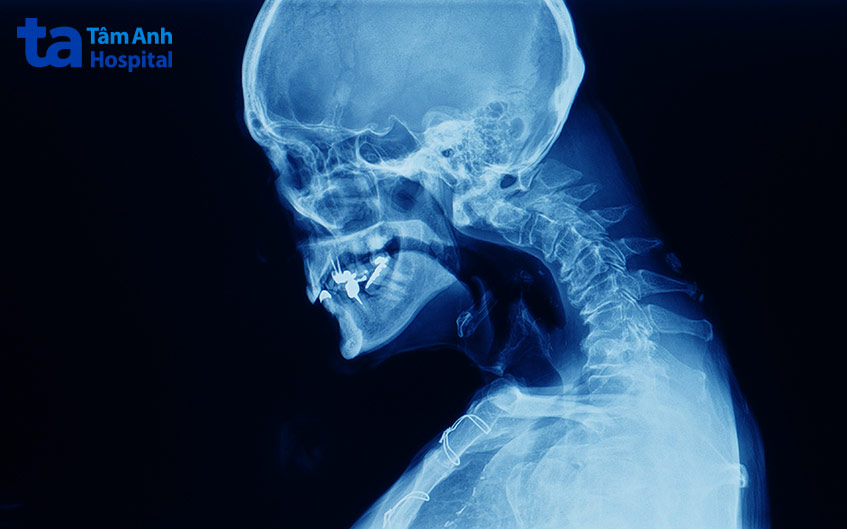

Gù lưng là tình trạng phần lưng trên bị biến dạng do cột sống cong quá mức về phía trước. Mọi lứa tuổi đều có thể bị gù, đối với người già, gù thường xuất hiện do xương không còn chắc khỏe, đốt sống bị xẹp lún. Trong khi đó, nguyên nhân gây gù lưng ở trẻ sơ sinh và thanh thiếu niên thường xuất phát từ dị tật hoặc tình trạng chèn ép cột sống theo thời gian.

Đa phần các trường hợp gù nhẹ không phải là vấn đề đáng lo ngại. Người bệnh chỉ cần tập vật lý trị liệu hoặc đeo nẹp để điều chỉnh tư thế và tăng cường sức mạnh cột sống. Tuy nhiên, nếu gù làm biến dạng cấu trúc, gây đau đớn, ảnh hưởng đến hô hấp, bác sĩ có thể chỉ định phẫu thuật để điều chỉnh, tránh biến chứng nghiêm trọng về sau. (1)